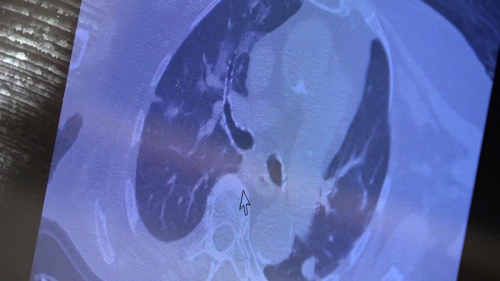

SAMSUN - Göğüs Hastalıkları Uzm. Prof. Dr. Şevket Özkaya, "Şu an 'aşı oldum hastalandım' diyenlerin büyük bir kısmı 'subklinik' olarak virüsle enfekte iken aşı olan grubu oluşturuyor" dedi. Göğüs Hastalıkları Uzm. Prof. Dr. Şevket Özkaya, 'omicron' varyantının ve aşılanmanın artmasıyla yeni sorunlar ve sorularla karşılaştıklarını söyledi. Hastaların polikliniklere "Hocam, biz 2 hafta önce aşı olduk, aşı olmamıza rağmen kovid olduk" şeklinde soruyla geldiklerini ifade eden Prof. Dr. Şevket Özkaya önemli açıklamalarda bulundu. "Lütfen aşı olmadan önce kendinizi değerlendirin" Hemen hemen herkeste semptom vermeyen düzeyde virüs yükü olduğuna dikkat çeken Dr. Özkaya, "Özellikle vatandaşlarımızdan aşı olurken kendilerini iyi değerlendirmelerini istiyoruz. Öyle vakalar geliyor ki 'hocam biz 2 hafta önce aşı olduk, aşı olmamıza rağmen kovid olduk' diyen hastalar var. Ülkede hemen hemen herkeste subklinik yani şikayet yapmayan semptom vermeyen düzeyde de olsa virüs yükümüz var. Üzerine aşı olduğumuz zaman bu klinik aşikar hale geliyor ve doktora, hastaneye gelmekle sonuçlanıyor. Bunların bir kısmında gerçekten akciğer tutulumu da görüyoruz. Eğer kendiniz halsiz, yorgun, kırgın hissediyorsanız ve yakın çevrenizde pozitif vakalarla temasınız varsa lütfen aşı olmadan önce kendinizi değerlendirin. Birkaç gün gözlemledikten sonra aşınızı olmanızı istiyoruz. Yoksa kovid virüsü ile enfekte iken üzerine aşı olduğunuzda semptomatik hale geliyor ve özellikle iş gücü kaybı, panik hali oluyor. Hastalar 'aşı oldum, hasta oldum' kaygısı yaşıyorlar. Aslında öyle değil. Ülkemizde hemen hemen herkeste subklinik semptom vermeyen düzeyde de olsa hepimiz bu virüsle karşılaşıyoruz. Üzerine aşı olduğumuzda aşının oluşturduğu hafif kırgınlık ve ateşle beraber hastalık ortaya çıkmaya başlıyor. Şu ana kadar bu kadar vakalar artmasına rağmen ölüm sayılarının az olmasını ve hastaneye yatışların azalmasını aşıya bağlıyoruz. Her seferinde şunu tekrarlıyoruz: Aşı emniyet kemeri gibidir. Sizi kaza yapmaktan ya da hastalıktan korumaz ama kaza yaptığınızda veya hastalığa yakalandığınızda hayatta kalmanızı sağlayacak" diye konuştu. 81 yaşında akciğer tutulum olan hastanın tomografisi Karşılaştıkları bu yeni hasta profilini örnek vererek açıklayan Özkaya, "81 yaşındaki bir hasta. Ailesinde kovid pozitif biri varken panik yaparak aşıya gidiyor. Sonrasında hızla akciğer tutulumu olan bir hasta ile karşılaşıyorsunuz. Bu şekilde ailenizde pozitif biri varsa ve kendinizde halsizlik kırgınlık hissediyorsanız panik yapmadan önce doktora gitmenizi sonra aşı olmanızı istiyoruz. Şu an 'aşı oldum hastalandım' diyenlerin büyük bir kısmı subklinik olarak virüsle enfekte iken aşı olan grubu oluşturuyor" şeklinde konuştu.